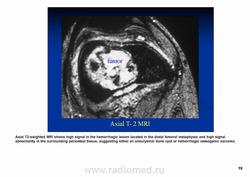

Телеангиэктатическая остеосаркома относится к остеолитическим вариантам обыкновенной интрамедуллярной остеосаркомы и содержит кистовидные сосудистые полости, разделенные тонкими костными перегородками. В некоторых случаях эта опухоль симулирует аневризматичесую костную кисту. Частота такого варианта составляет 0,4—12 % от общего числа остеосарком. Патологический перелом к моменту диагностики встречается более чем у 25 % больных, тогда как лиц с обыкновенной остеосаркомой — не более чем 5 %. У пациентов старшей возрастной группы, а также лиц с поражением костей осевого скелета развитие телеангиэктатической остеосаркомы происходит на фоне болезни Педжета. Макроскопически эта опухоль имеет вид то крупного сгустка крови или некротической массы, то многокамерной кисты, содержащей жидкую кровь, как это бывает в аневризматической костной кисте.

Рентгенологически выявляют метафизарную локализацию, полностью литическое поражение без признаков оссификации, часто интенсивное вздутие кости и её деструкцию, формирование мягкотканого компонента, иногда периостальную реакцию.